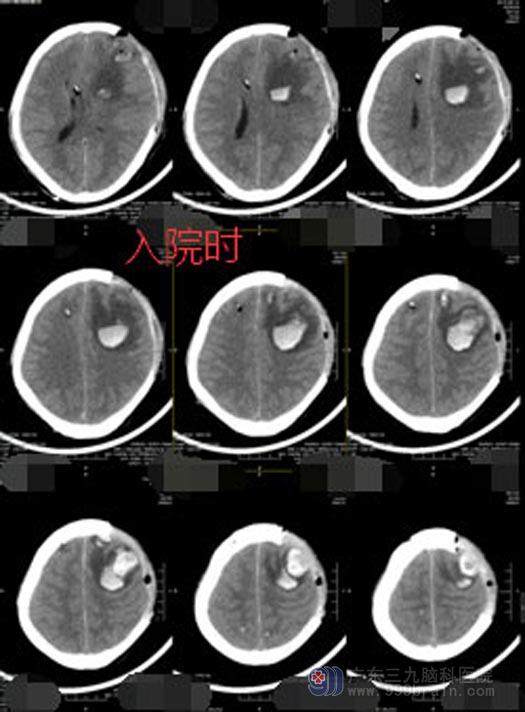

陈大哥是一名工地建筑工人。一次高空作业中不慎从6米高的地方坠落,头着地,当时便不省人事。立即被送到当地医院急诊科,头颅ct提示:“左侧额叶脑挫伤,左额颞顶部硬膜下血肿,右颞顶枕骨骨折”,急诊全麻下行“右侧脑室颅内压监测探头植入+左额颞顶部开颅,硬膜下、脑室内血肿清除术+硬膜外修补术+去骨瓣减压术+右侧枕及颌下部伤口清创缝合术”。

广东三九脑科医院副院长、神经外五科主任鲁明详细了解患者病情、仔细查体后认为病人是有好转希望的。头颅CT检查显示脑水肿,入院当日立即行“左额颞血肿清除术+内减压术”,术后病人身体较弱,送ICU 监护,患者痰多,又持续高热,胸部CT提示肺部感染严重,进行抗感染的同时给予纤支镜治疗,经过多日的精心护理,陈大哥总算睁着眼睛从ICU出来了。虽然对外界仍没有反应,但是总算看到了希望。继续进行高压氧、针灸、推拿等康复促醒治疗后,陈大哥终于清醒了过来。

▲入院时CT